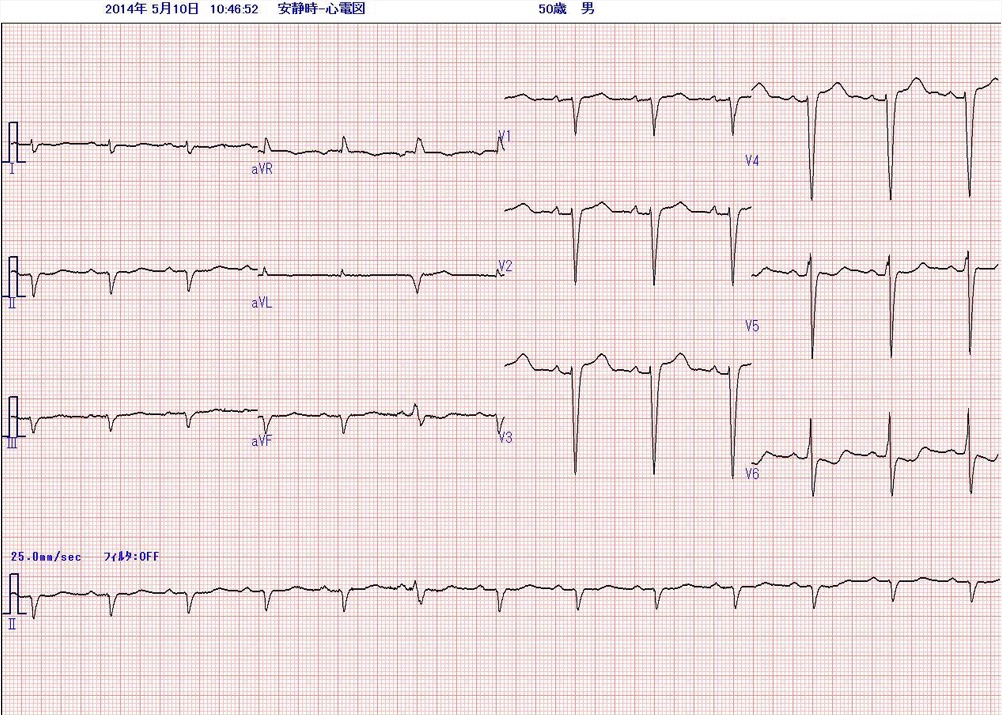

来院時にとられた心電図(1)と6年前に胆嚢炎で入院した時の心電図(2)を示します。

心電図(1)来院時

心電図(1):四肢low voltage、陳旧性前壁中隔梗塞疑い、心室内伝導遅延、左軸偏位、非特異的STT異常

心電図(1)は、正常洞調律(心拍数75/分)、P波に異常なく、PQ間隔は0.20secである。QRS波は四肢誘導にてlow voltageである。

胸部誘導では、V1〜4でr波の増高が乏しく、陳旧性前壁中隔梗塞の存在が疑われる。QRS波は0.12秒と幅広い。Ⅰ誘導で幅広いS波、aVRで幅広いr波を認め、

完全右脚ブロックのようにも見えるが、V1誘導はrS型で遅延したr‘はみられず、胸部誘導ではむしろ左脚ブロックのようにもみえる。これは心室内伝導遅延と呼ばれるもので、心室筋が瀰漫性に障害されている所見である。QRS電気軸は-107度と極端な左軸偏位を示している。非特異的STT異常がみられる。

aVR、aVL、aVF誘導では第3心拍、最下段に示したリズム記録では、第6心拍においてQRS波形が変化している。先行するP波の形がわずかに変化しており、

PQ間隔が短縮していることから、心房性期外収縮と考えられる。このわずかな心拍の変化でも、心室内伝導が影響されQRS波が変化するような状況がある。

両者の比較で、5年の間に、①QRS voltageが全体に低下した、②胸部誘導でr波が明らかに減少した(陳旧性前壁中隔梗塞様所見)、③心室内伝導遅延がおこっている、④非特異的STT異常が認められる。 病歴から過去に心筋梗塞を起こした様子はない。受診時の血圧は102/76mmHgと低下している。急激に進行する左心不全と左室電位の低下、心室内での瀰漫性の伝導障害を総合すると、過去5年間に心臓全体に変性病変が起こり心機能が低下したことが考えられる。